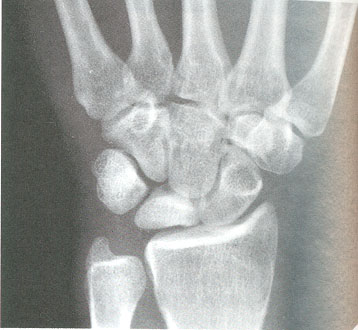

Figura 4: semilunar con esclerosis radiológica y pérdida de altura. Cúbito minus

Junto con los síntomas y la exploración física, es necesario realizar pruebas de imagen radiológicas. En la radiografía simple se pueden observar cambios en la densidad ósea del semilunar y las variantes morfológicas óseas (figura 4).

La resonancia nuclear magnética (RNM) es la prueba diagnóstica más útil porque permite el diagnóstico precoz de la enfermedad de Kienböck y evalúa los resultados tras la cirugía (figura 5). La tomografía axial computarizada (TAC) permite valorar mejor la estructura ósea y un estadiaje más preciso.